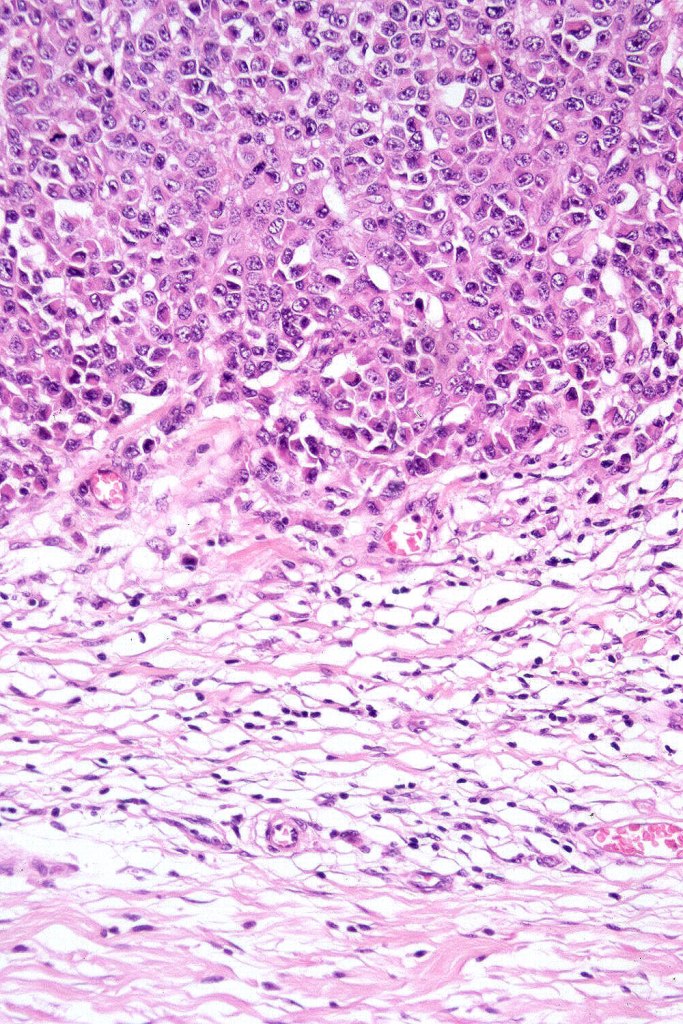

•Characterized by pleomorphic tumor cells with large eosinophilic, hyaline globular inclusions and eccentric vesicular nuclei containing prominent nucleoli, mitoses often conspicuous

•Inclusions predominantly composed of vimentin intermediate filaments

•Very sparse melanin pigment may be identified

In this example, rhabdoid change accounted for only a small component of the tumor. IHC is S100